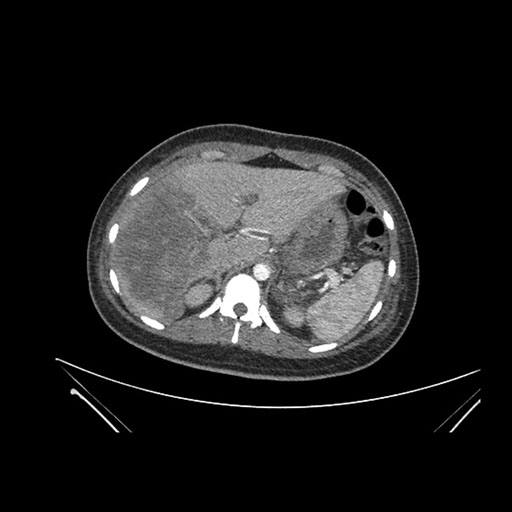

Axial Arterial

Axial Venous

Coronal Arterial

Coronal Venous